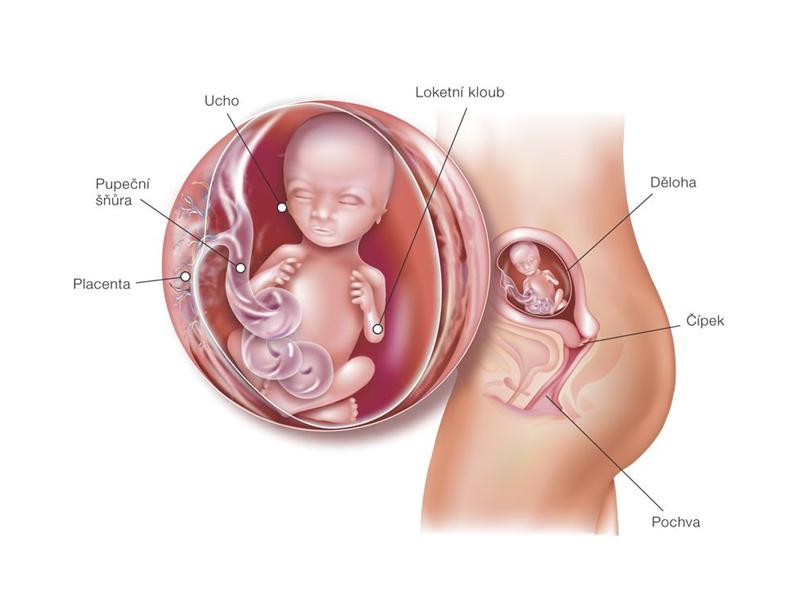

Zuzana se v 18. týdnu těhotenství. Co se děje s jejím tělem?